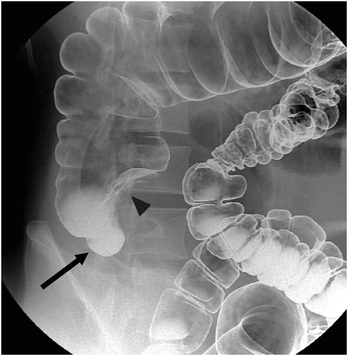

Six months later, he visited the outpatient clinic and complained of sustained right lower abdominal discomfort. He had experienced considerable hematochezia one month before visiting the outpatient clinic, but it had subsided without any symptoms, other than the right lower abdominal discomfort. As a result of the hematochezia and sustained right lower abdominal discomfort, we recommended surgery. A colon study showed a diverticulum and external compression in the cecum without any polypoid mass and diverticulum in the colon (Fig. 2).

Fig. 2

Colon study finding. There is a diverticulum (arrow) and an external compression (arrowhead) in the cecum. There is no other diverticulum noted in the colon.